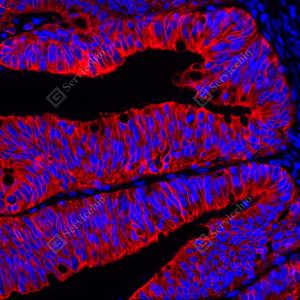

IF检测Cytokeratin 18蛋白(货号 GB15232)(红色). 样品: 人结肠癌, 4%多聚甲醛 (货号G1101) 固定12-24小时. 抗原修复: 柠檬酸抗原修复液(干粉, pH 6.0) (G1201), 高压锅均匀喷气计时2分钟. 封闭: 3% BSA(货号GC305010)的PBS溶液, 室温孵育30分钟. —抗: 1: 1000稀释, 4℃ 孵育过夜. 二抗: Cy3标记山羊抗小鼠IgG (H+L) (货号GB21301), 1: 300稀释, 室温孵育1小时. |